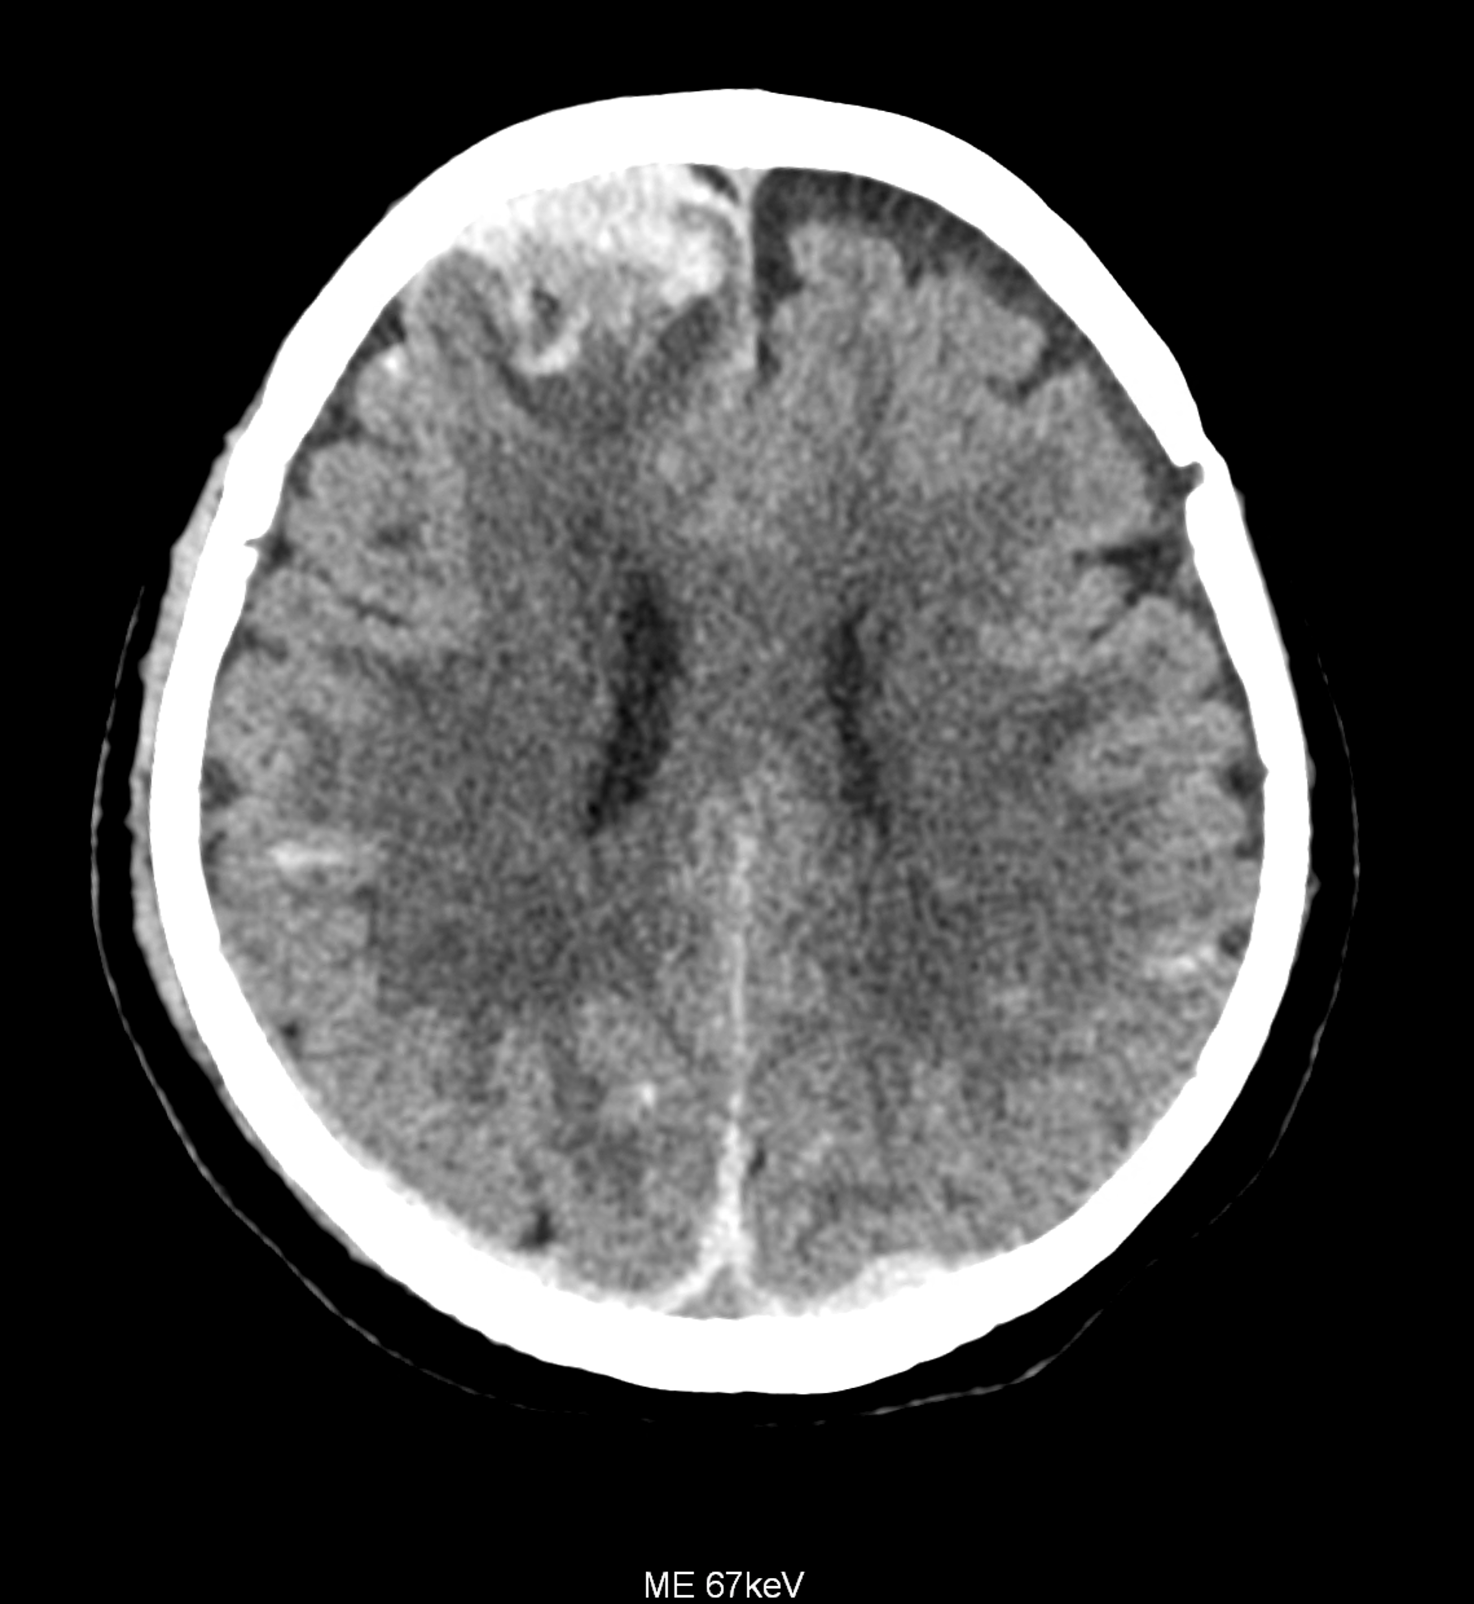

An example of the use of spectral imaging in complex brain injury, where contusions, diffuse axonal injury, subarachnoid hemorrhage, subdural hemorrhage, and blood in the ventricular system are present.

comparison of the images with the energies of monoenergetic reconstructions 40 keV, 67 keV (standard conventional reconstruction), 190 keV and virtual non contrast (VNC)

Bleeding is characterized by different absorption characteristics than healthy brain tissue (both gray and white matter) and cerebrospinal fluid. Due to the higher proportion of proteins with amino acids with disulfide bonds, the signal intensity increases at higher energies, making it possible to use monoenergetic imaging at energies above 140 keV, and/or virtual non-contrast. The hemorrhage then becomes more hyperdense, while the rest of the brain tissue acquires a uniform low signal. In addition to bleeding, areas of extracellular fluid of vasogenic origin are also imaged, i.e., in areas around contusion-type brain tissue injuries.